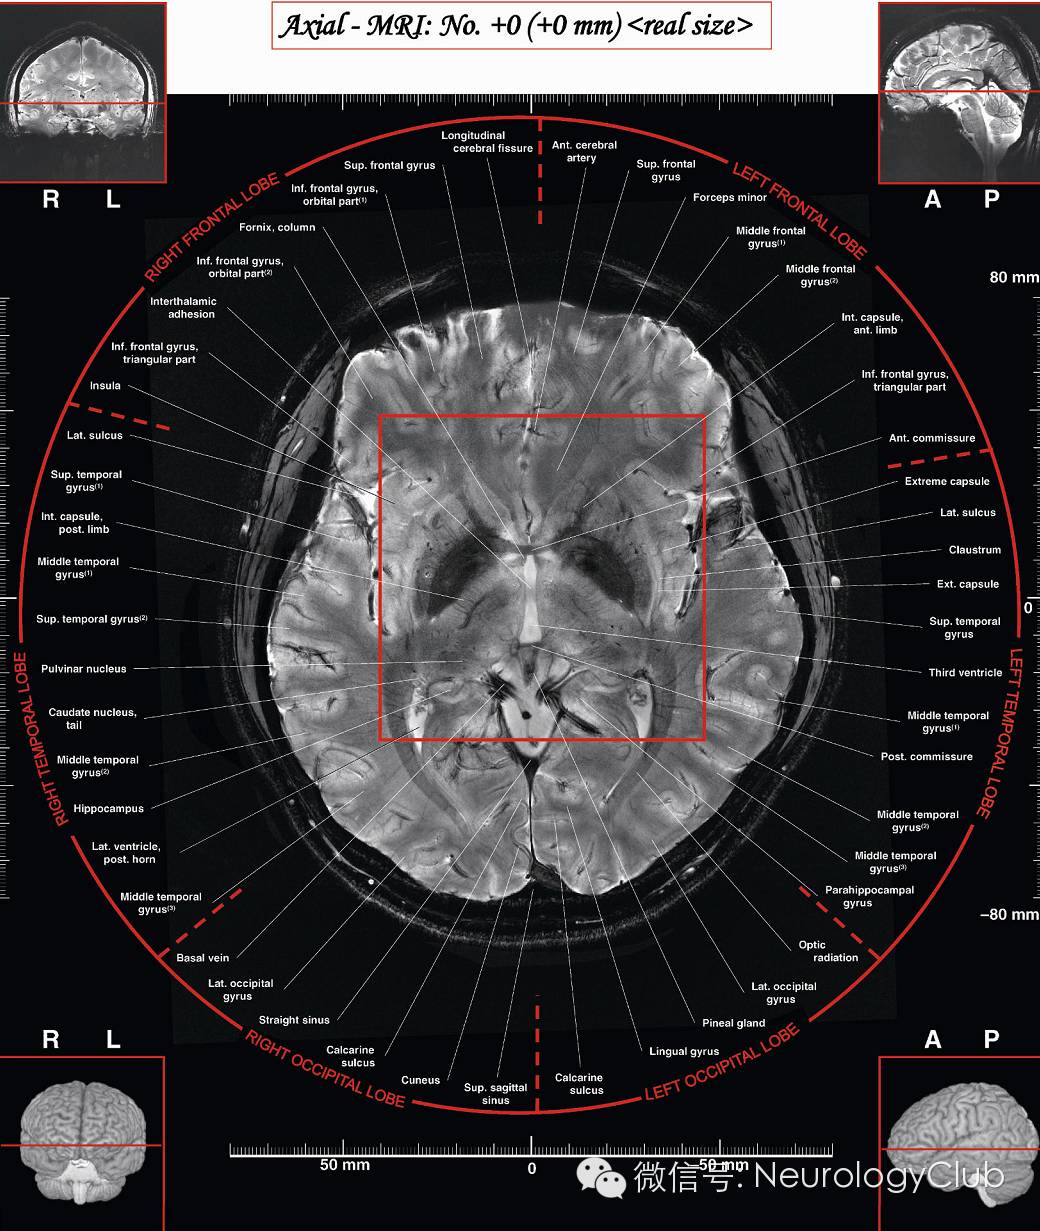

(图4:基底节区解剖示意图。引自:Head and Neuroanatomy.Thieme Medical Publishers Inc;1st ed. 2010)

(图5:7T磁共振下的基底节区结构。引自:7.0 Tesla MRI Brain Atlas. Springer; 2nd ed. 2015)